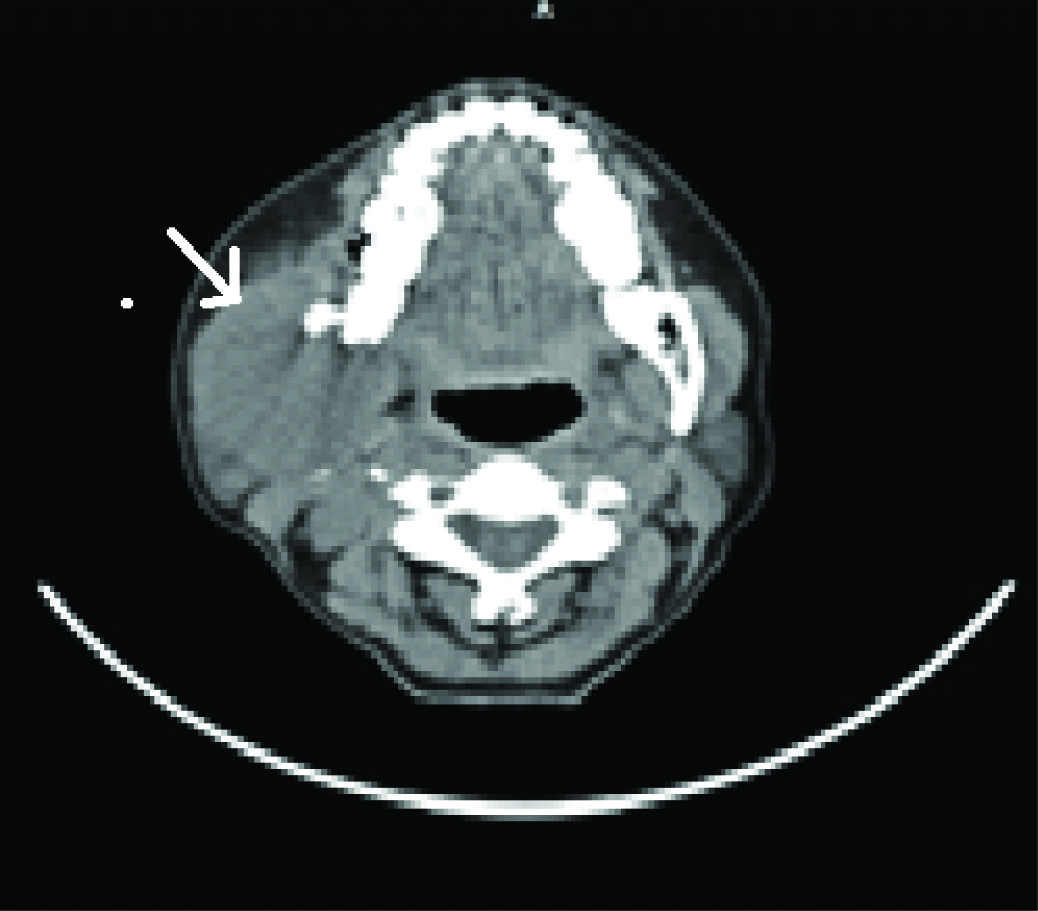

CT scan [Table/Fig-3] revealed an osteolytic lesion with predominantly soft tissue mass measuring 6.2 cm X 4.0 cm on the right ramus of the mandible. 3–D CT [Table/Fig-4] confirmed the OPG findings and depicted a pronounced destruction of bone at the angle and posterior border, with destruction of medial and lateral cortices. This Sectionmade us clinically diagnose a fast growing solid tumour in the ramus. The clinical differential diagnosis included odontogenic tumours, neural sheath tumour and secondary metastasis from elsewhere.

Axial view of ct scan showing the lession on the right ramus of the mandible